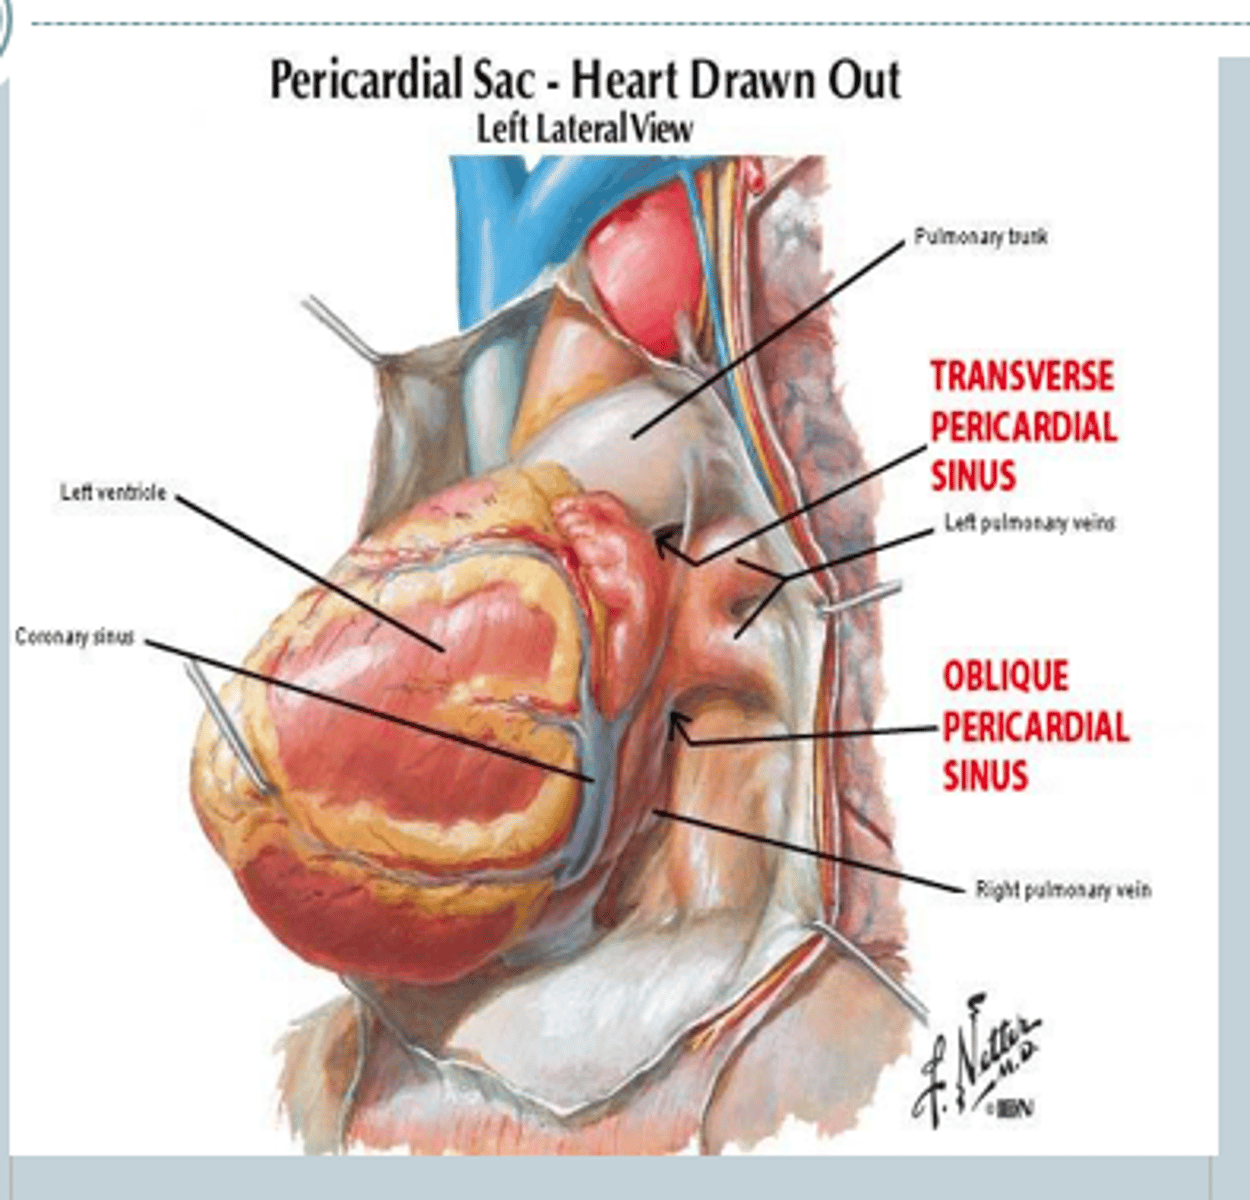

Co to są zatoki osierdzia?

zachyłki jamy osierdzia występujące między dużymi naczyniami krwionośnymi

Co znajduje się na dużych naczyniach krwionośnych sąsiadujących z zatokami osierdzia?

linia przejścia blaszki ściennej w blaszkę trzewną

Wymień duże zachyłki osierdzia

zatoka poprzeczna i zatoka skośna

zatoka poprzeczna osierdzia

transverse sinus of pericardium

zatoka poprzeczna osierdzia - położenie

za aortą wstępującą i pniem płucnym od przodu i żyłą główną górną i prawym przedsionkiem od tyłu

Co pokrywa zatokę poprzeczną osierdzia od góry?

blaszka ścienna osierdzia surowiczego

zatoka skośna osierdzia

oblique sinus of pericardium

zatoka skośna osierdzia - położenie

między żż. płucnymi lewymi (po lewej) i żż. płucnymi prawymi i ż. główną dolną (po prawej)

Po której stronie jest wejście do zatoki poprzecznej?

po prawej i lewej

Po której stronie jest wejście do zatoki skośnej?

od dołu